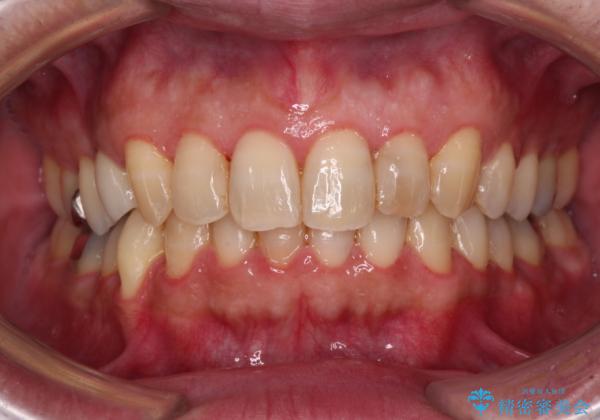

外側に飛び出した歯 インビザラインによる矯正治療

- 外に飛び出した側方の歯と、前歯のデコボコを気にして来院された患者様です。

IPR(歯と歯の間を削る)によってデコボコが解消するように設計し、インビザラインにより治療を行うこととしました。

治療途中で1年半以上通院されない時期があったため、後戻りが生じたことで治療期間が長くなってしまいました。

親知らずを抜去したことで、下顎のデコボコがきれいに解消されました。